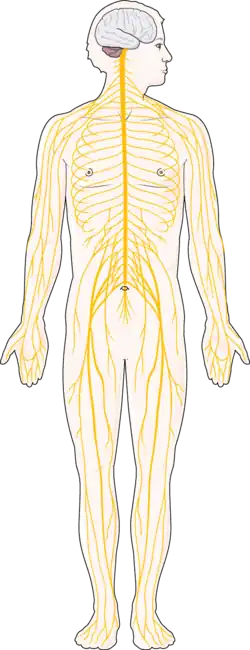

Chronic neuropathic pain is caused by a disease or lesion of the somatosensory nervous system. Chronic neuropathic pain requires a history of nervous system injury or disease as well as a distribution of pain that makes sense in the context of neuroanatomy.[22]

Chronic central neuropathic pain

Chronic central neuropathic pain is caused by a lesion or disease of the central somatosensory nervous system.[23]

Chronic peripheral neuropathic pain

Chronic peripheral neuropathic pain is caused by a lesion or disease of the peripheral somatosensory nervous system.[22]

Chronic secondary musculoskeletal pain due to disease of the nervous system

Chronic secondary musculoskeletal pain due to disease of the nervous system is associated with central or peripheral nervous system conditions that are categorized elsewhere. It involves pain brought on by changes in sensory and motor function.[30]